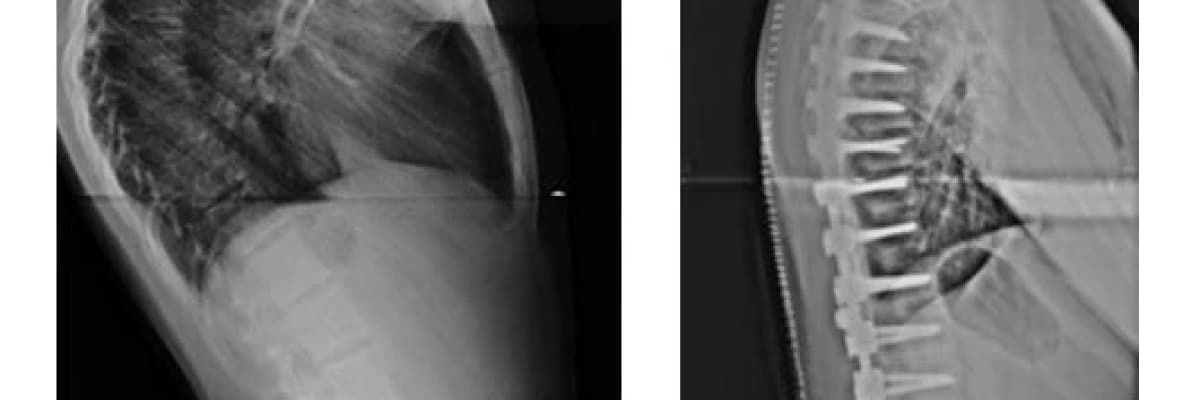

Kifozun cerrahi tedavisi nasıl yapılır?

Eğimin çok arttığı hastalarda (75 derece ve üstü) cerrahi tedavi tercih edilir. Cerrahi ile kamburluk düzeltilir ve eğikliğin ilerlemesi durdurulur.